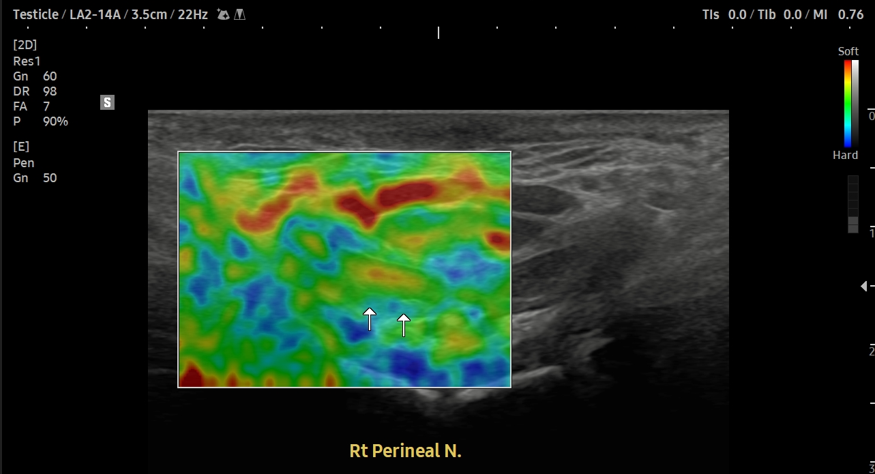

- 치료기간 : 25 . 10 . 10 ~ 25 . 12 .11

- 치료횟수 : 10 회(아피톡신+극초단파)

치료 전

치료 후